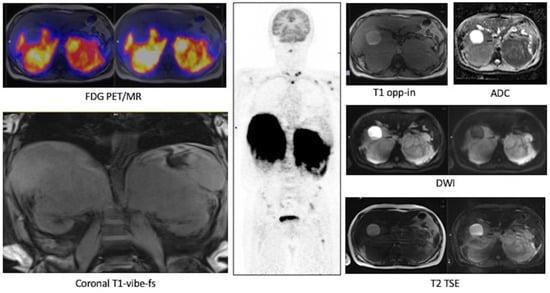

3.2.2. Restaging: Case #2

3.2.3. Evaluation of Response to Therapy: Case #3, Case #4 and Case #5

Case #3

Case #4

Case #5